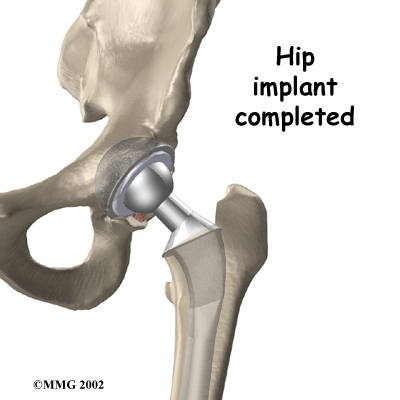

Artificial Hip Replacement

An artificial hip replacement is the ultimate solution for advanced hip OA. Surgeons prefer not to put a new hip joint in patients less than 60 years old. This is because younger patients are generally more active and might put too much stress on the joint, causing it to loosen or even crack. A revision surgery to replace a damaged joint is harder to do, has more possible complications, and is usually less successful than a first-time joint replacement surgery.

Related Document: Ari Levine PT, PC's Guide to Artificial Joint Replacement of the Hip